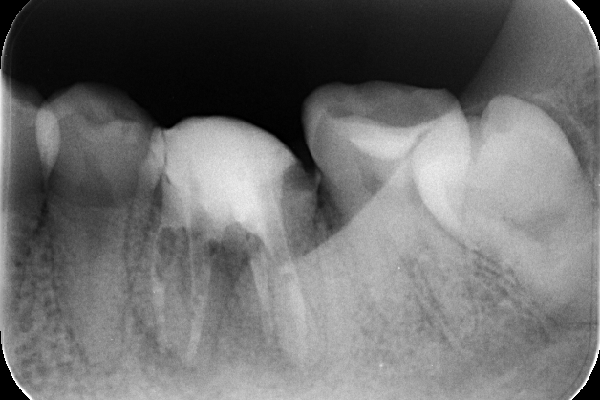

レントゲン解説:4根管すべてに根管充填が密にされていることを確認できる

透過像は消失し、明らかな骨形成を認める。(黒い影の消失)